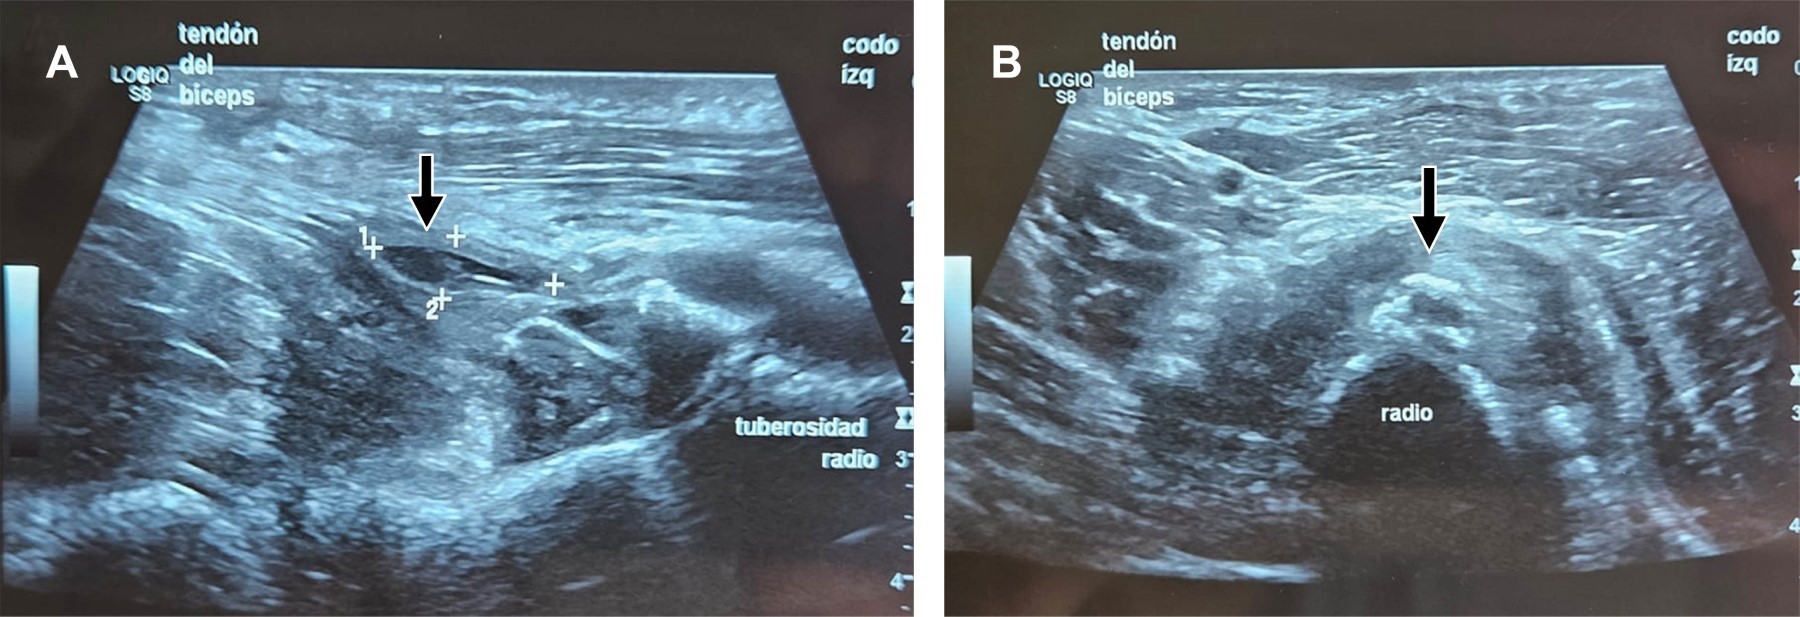

Avulsion fracture of the distal tendon of the biceps brachii (TDB) is rare, with an incidence of 5.35 per 100,000/year. It is observed in athletes performing a forced eccentric brachial biceps contraction. The injuries are evaluated with the "hook test". Tendon repair is performed in acute injuries involving > 50%. Usually, reinsertion through an incision is performed by fixation to the second cortex with a "button" type device. There is no consensus on the best repair method; surgical complications are heterotopic ossification, rigidity, external cutaneous neuropraxia of the antebrachial nerve, and injury to the posterior interosseous branch of the radial nerve.

Figure 1